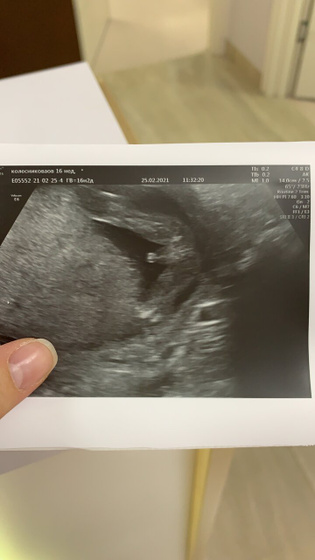

Всем привет. Была сегодня цервикометрия и заодно пол посмотрели. Уже точно 100% мальчик!? БПР намерили аш на 18 недель. Походу умный будет? головное предлежание (это я так поняла головой вниз лежит))) Правда шейка все таки подвела. Намерили всего 29 мм. В понедельник едем зашивать. Перевели на 3 утрожестана по 200 обратно. Мне ещё на гсг при проверке проходимости труб врач говорила есть подозрение на ицн, следи. Ну она и была права. Ну думаю это ничего страшного. Главное что вовремя предотвратим и все будет хорошо.❤️ Девочки, кому зашивали шейку? Как там? Как это? Расскажите неопытному пожалуйста ?

У нас тоже есть такое фото. С рогаткой?

УЗИ прикольное) чего не хотят на Утрожестан понаблюдать в стационаре недельку… шьют когда 20-24 мм… девочка лежала на 20 неделе, наблюдали, типа гкнферона ещё свечки лев делала, шейка увеличилась и отпустили.